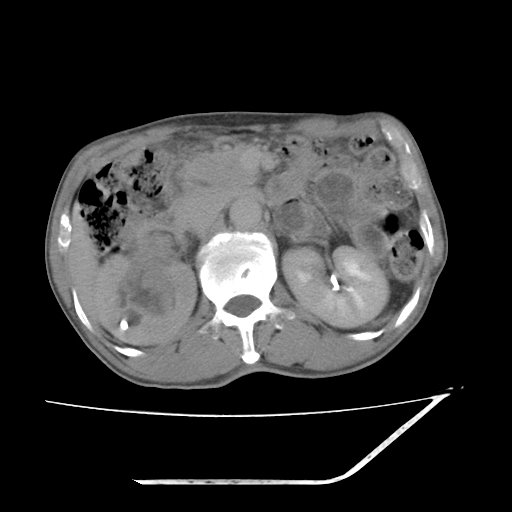

平扫

考虑右肾盂癌,肾动脉受侵,右肾功能减退,右肾盂输尿管积水,管壁增厚,考虑种植转移,应该把下面扫完的

支持右侧肾盂癌伴肾静脉瘤栓形成可能性大,右肾结石.肝右叶后段低密度影,不除外转移.

考虑右肾盂癌,肾动脉受侵,右肾功能减退,右肾盂输尿管积水,管壁增厚,考虑种植转移  支持

考虑右肾盂癌,右肾功能减退,右肾盂输尿管积水,管壁增厚,考虑种植转移  支持

右肾盂旁ca并肾静脉瘤栓形成/肾功能降低。

右肾结石。

右肾盂癌,肾动脉受侵,右肾盂输尿管积水,管壁增厚,考虑种植转移

右肾盂移行细胞癌并右输尿管中段转移.肾积水.

支持 右侧肾盂癌伴肾静脉瘤栓形成可能性大,右肾结石;肝右叶后段低密度影,不除外转移。

1.右侧肾盂癌伴肾盂积水。

2.肾脏功能减退,原因有:(1)肾动脉受侵。(2)肾静脉受侵(3)肾积水,等。本例,肾动脉显影较好,但受压明显;肾静脉无明显显示,受压或静脉癌栓,下腔静脉腔内未见明显充盈缺损。

3.右侧上段输尿管扩张,原因:(1)积水所致;(2)种植。